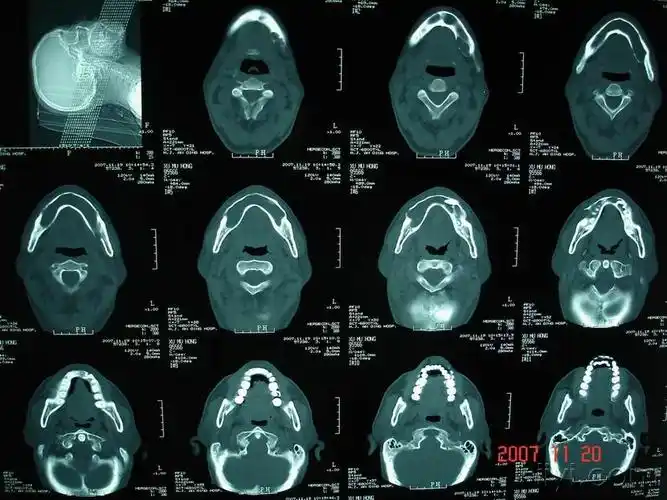

某男性患者,29岁,无意中发现左下颌骨较对侧隆起,ct如图所示,最可能的

下颌骨占位分析-ct--已公布答案:4月27日

下颌骨病变

口腔颌面部ct诊断